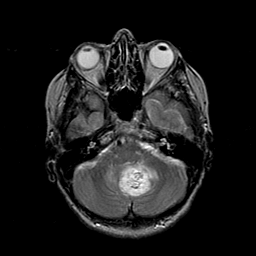

Metastatic Adenocarcinoma of the Colon: T2-weighted MR -- Slice #6

[Home][Help][Clinical] Slice 6